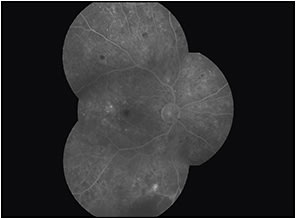

At the first visit, ordering FFA (especially when the BCVA is approximately 20/20) is important (Figures 11 and 12) because it will help us to document the presence of clinically significant macular edema (CSME) as defined by the ETDRS, and the measurement of VA is insufficiently sensitive to detect DME.3 Treating such cases with focal laser photocoagulation may maintain good vision for approximately 18 weeks in cases of good control of diabetes and blood pressure.

Figure 11. Fundus photo of the eye of a patient with DME and BCVA of 20/20.

Figure 12. Image from the same patient as in Figure 11, showing focal leakage and clinically significant edema.

Ordering FFA at the first visit is mandatory in cases of featureless retina with very poor BCVA to exclude ischemic DME because these patients have poor prognoses and will not benefit from any treatment in which OCT cannot detect ischemic diabetic maculopathy4 but may show evidence of ganglion cell layer damage.5

Fundus FA can be ordered as a guide for locating leaking microaneurysms. Further, in cases of CSME, when planning to perform laser photocoagulation, FFA can be performed either promptly (at one week) or deferred (at 24 weeks) until after intravitreal injections (anti-VEGF or steroids), depending on the case.